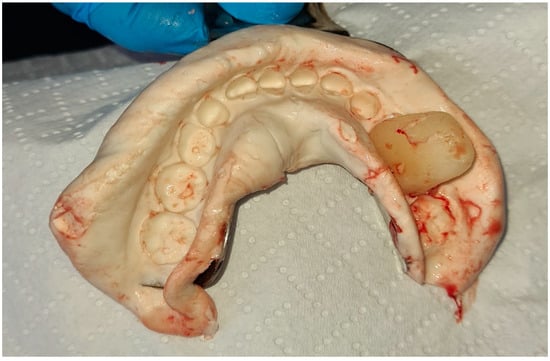

2. Case Report

3. Follow-Up and Outcomes